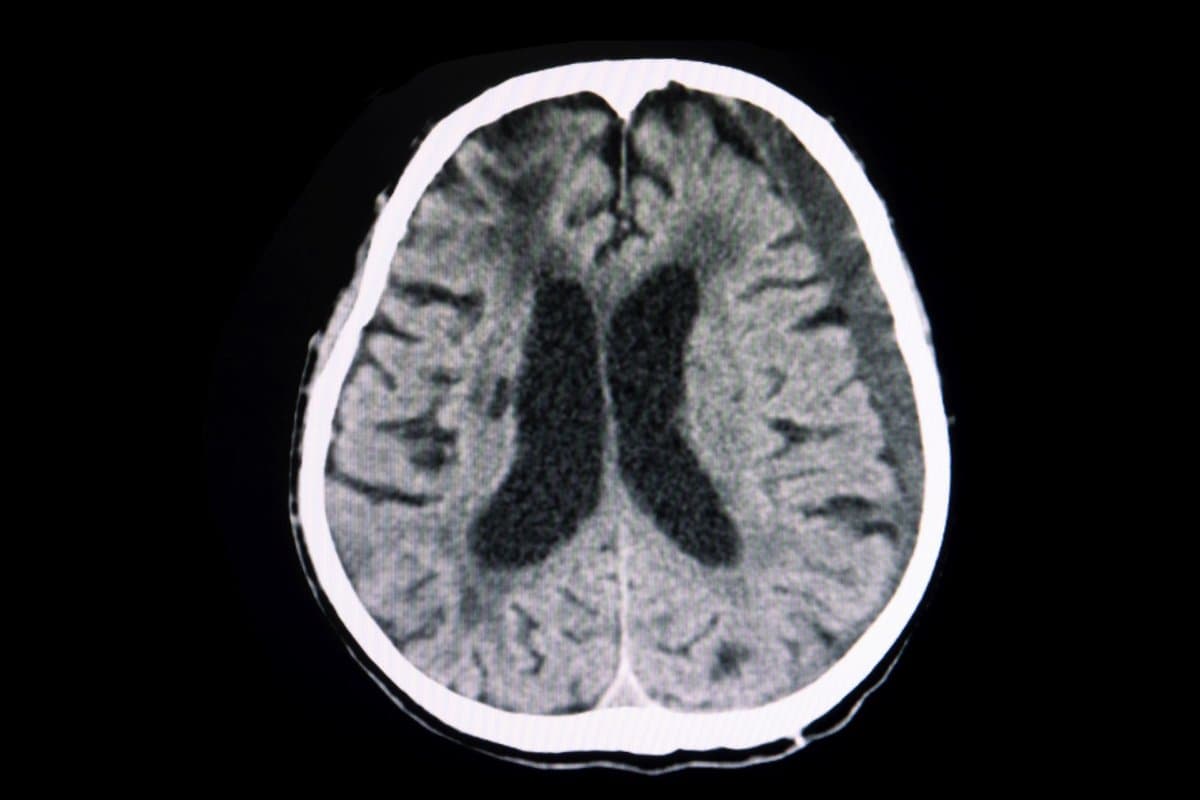

Subduralhämatom: Kann Dexamethason die Operation ersetzen?

Bisher hat man ein chronisches Subduralhämatom über ein Bohrloch im Schädelknochen entfernt. Holländische Forscher untersuchten nun, ob es auch weniger intensiv allein mit Glukokortikoiden geht. Der Erfolg des Vorgehens hielt sich allerdings in Grenzen.

Die Häufigkeit des chronischen Subduralhämatoms nimmt angesichts der alternden Bevölkerung und des breiten Einsatzes von Antikoagulanzien zu. Die Standardbehandlung besteht in der Entfernung des Hämatoms über ein Bohrloch mit anschliessender Drainage der restlichen Hämatom-Flüssigkeit.